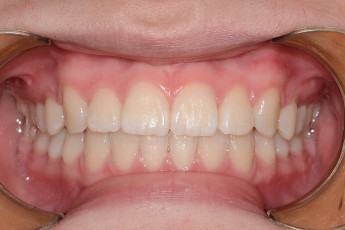

BEFORE & AFTER